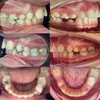

Diş Çapraşıklığı

Ortodonti